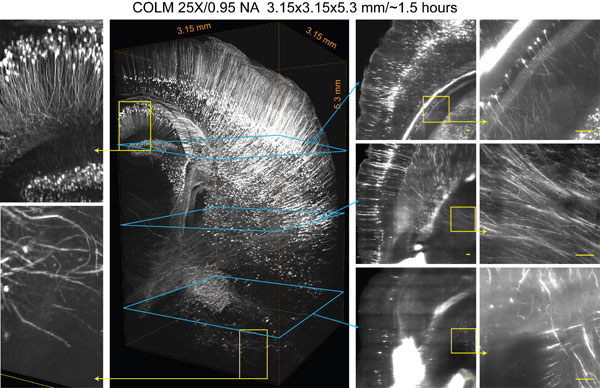

These advancements permit the imaging of a whole human brain at previously unprecedented resolution within about 220 days, as opposed to more than 80 years using the original CLARITY.

Here we describe protocols spanning multiple dimensions of the CLARITY workflow, ranging from simple, reliable and efficient lipid removal without electrophoretic instrumentation (passive CLARITY) to optimized objectives and integration with light-sheet optics (CLARITY-optimized light-sheet microscopy (COLM)) for accelerating data collection from clarified samples by several orders of magnitude while maintaining or increasing quality and resolution. The entire protocol takes from 7–28 d to complete for an adult mouse brain, including hydrogel embedding, full lipid removal, whole-brain antibody staining (which, if needed, accounts for 7–10 of the days), and whole-brain high-resolution imaging; timing within this window depends on the choice of lipid removal options, on the size of the tissue, and on the number and type of immunostaining rounds performed. This protocol has been successfully applied to the study of adult mouse, adult zebrafish and adult human brains, and it may find many other applications in the structural and molecular analysis of large assembled biological systems.